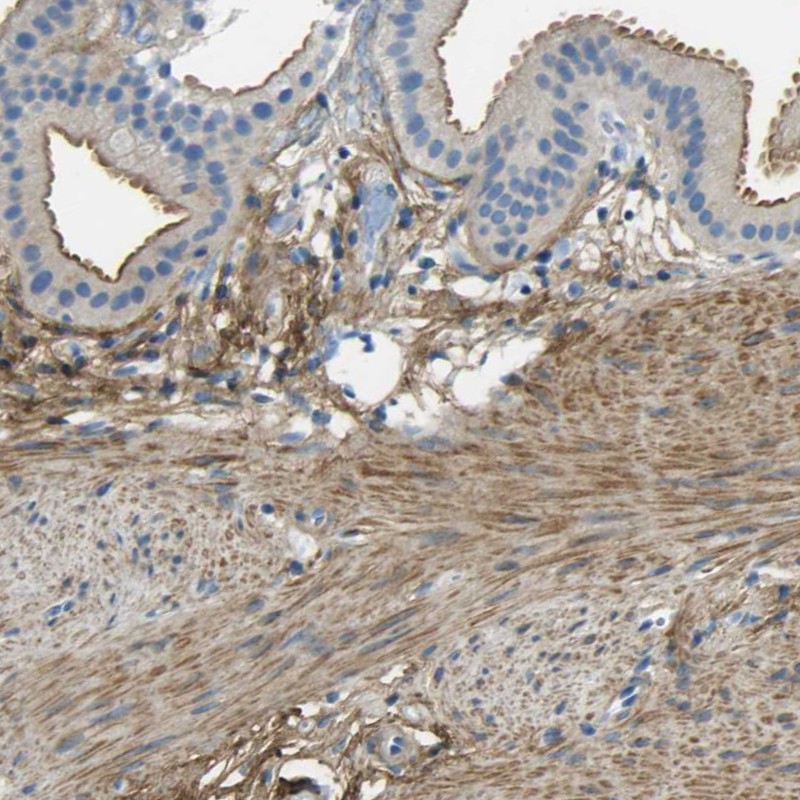

Immunohistochemical staining of human gallbladder shows moderate membranous positivity in glandular cells.